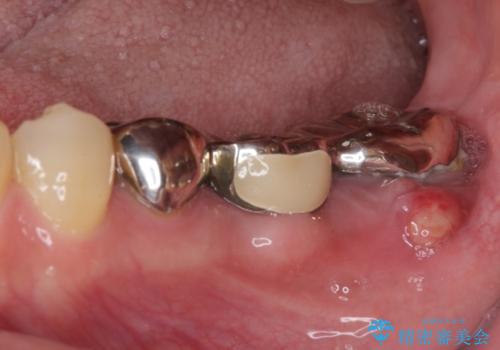

- 近医にてブリッジ治療を行った歯が痛くてたまらないとのことで来院された患者様です。

診察を行ったところ、奥の土台になっている歯は神経組織が失活しており、根尖部に病変があり、そこが原因で痛みを生じている状態でした。

根管治療を行うためにブリッジを除去したところ、むし歯が歯肉の奥深くにあまで及んでいたため、歯周外科処置によりむし歯が歯肉縁より浅い位置へと改善することとしました。